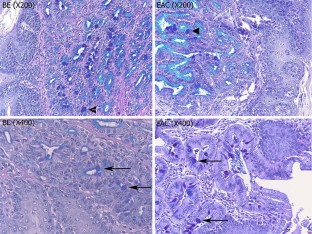

Morphological transformation from esophagitis (100% of animals) to BE (66% of animals) to EAC was observed after 3 months. There was marked loss of MnSOD expression in animals with esophagitis and BE at 1 and 2 months, with an increase in expression during the transformation to dysplasia and EAC. Increased proliferation and apoptosis was observed and reached a peak at months 1 and 2. Greatly increased levels of 8-hydroxy-deoxyguanosine was found during the progression to EAC.

FIG. 1.

FIG. 2.

FIG. 3.

FIG. 4.

FIG. 5.

FIG. 6.